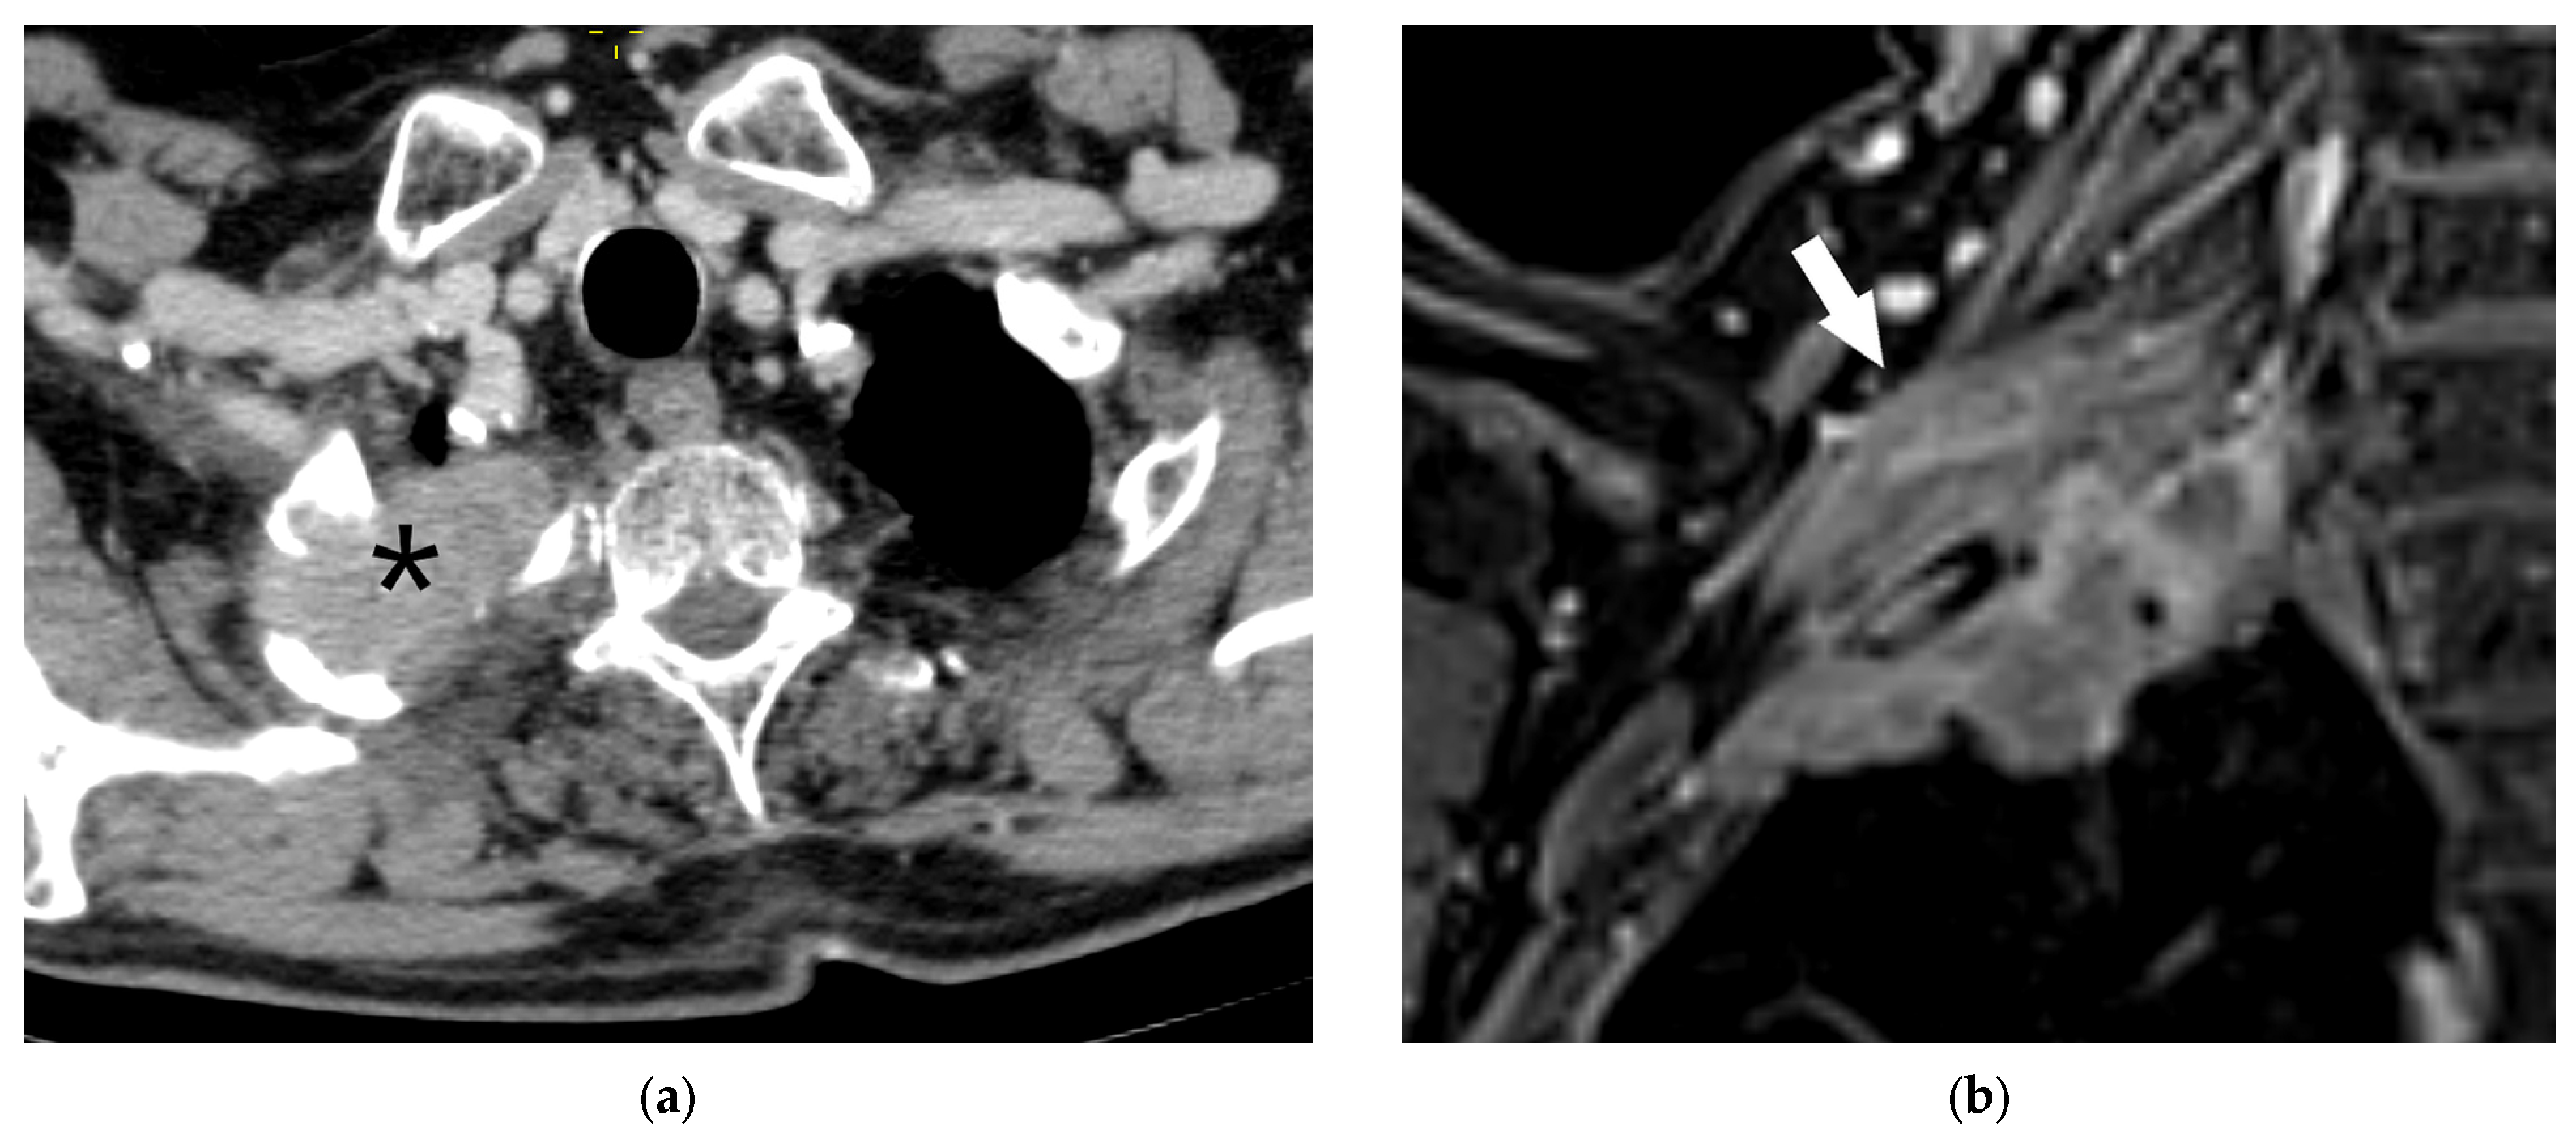

| T4 | Tumor > 7 cm in the greatest dimension Invasion of the mediastinum, thymus, trachea, carina, recurrent laryngeal nerve, vagus nerve, esophagus, or diaphragm Invasion of the heart, great vessels (aorta, superior or inferior vena cava, intrapericardial pulmonary arteries or veins), supra-aortic arteries, or brachiocephalic veins Invasion of subclavian vessels, vertebral body, lamina, spinal canal, cervical nerve roots, or brachial plexus Separate tumor nodule(s) in a different ipsilateral lobe than that of the primary | Signs of mediastinal invasion: infiltration of the mediastinal fat or structures that indicate the T4 stage, tumor–mediastinum contact length of more than 3 cm, an obtuse angle between the tumor and the mediastinum [37] Signs of vascular invasion: disappearance of the fat layer between the mass and the vessel, the angle between the mass and vessel wall >90°, a stenosis or deformation of the vascular lumen [41,42] |